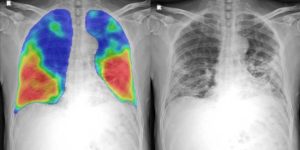

Bunun dışında nezle diye bilinen hastalık da burun akıntısıyla, gözlerde yanma ve kızarıklıkla, boğazda bir kaşınma hissiyle başlar. Öksürük genelde nezlede görülmez. Daha çok üst solunum yollarını etkileyen bir virüs enfeksiyonudur. Koronavirüsün belirtileri ile bunlar aslında çok benzer. Koronavirüs enfeksiyonunu diğerlerinden ayıran, daha önemli olmasını sağlayan özelliği alt solunum yollarından akciğerlere çok daha hızlı inip yayılabiliyor olmasıdır. Maalesef ağır tabloyu da zaten akciğer enfeksiyonu ve pnömoni yani zatürre yaparak oluşturuyor. Nezle gibi üst solunum yollarında sınırlı kalmıyor, alt solunum yoluna iniyor ve yüksek ateş tabii ki bunda da belirgin faktör. Diğerleri iştahsızlık, kilo kaybı gibi sorunlara yol açıyor. Bunlar hemen hemen hepsinde aynı.”